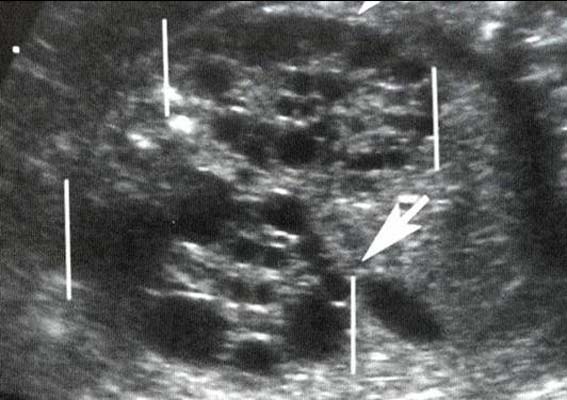

Echographiquement :

- Néphromégalie bilatérale

- Aspect hyperéchogène de la médullaire

- Kystes de petite taille de répartition non homogène pouvant atteindre la corticale